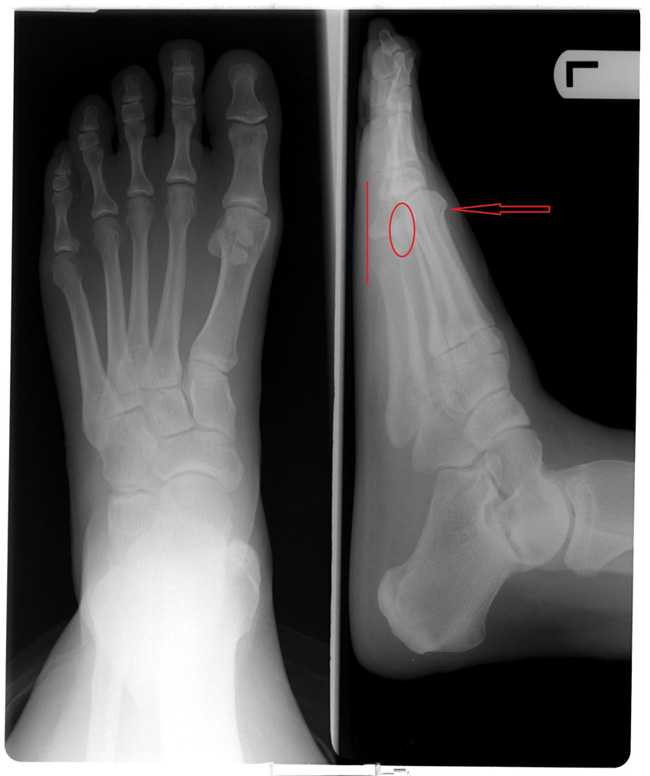

Dưới ảnh chụp X-quang, ta nhận thấy khi ngón thứ 2 "vượt cao" thì phần xương ngón chân cái cũng có xu hướng bị ép và cong vào sát với ngón trỏ.

Ảnh chụp X-quang

Phần đốt ngón chân ở xương ngón chân trỏ có phần dài hơn so với các ngón chân còn lại

Theo đó, ngay từ khi bẩm sinh, phần đốt ngón chân ở xương ngón chân trỏ có phần dài hơn so với các ngón chân còn lại. Điều này khiến cho ngón trỏ có xu hướng dài hơn các ngón còn lại trong bàn chân.